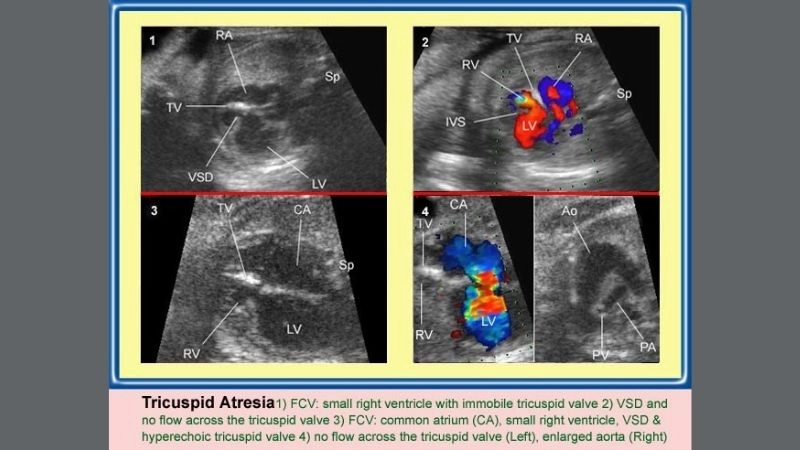

Images visual examples of hypoplastic right heart syndrome (HRHS)

Hypoplastic right heart syndrome (HRHS) is a rare congenital heart defect where the right side of the heart is underdeveloped, impairing blood flow to the lungs.